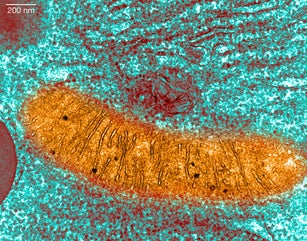

Build confidence for lab experiments with this Kahoot collection. It covers the foundations of research for biology students in high school. It includes Kahoots about scientific method, metric system, proper measurement techniques, microscope use, and key lab equipment. #biologybasics #labskills #scientificmethod #microscope #metricsystem #measurement #biologytools #science #fun #awesome #biologyfoundation #experiments #sigfigs #inquiry #observation